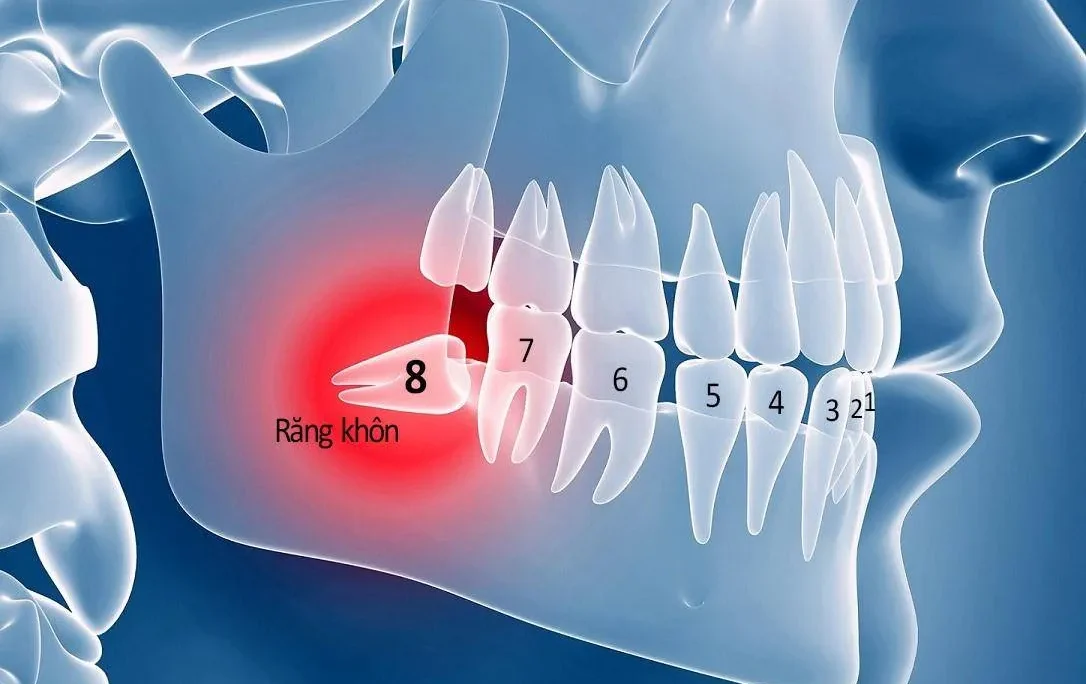

- Răng bị sứt mẻ lớn: Một số trường hợp răng bị sứt mẻ quá 2mm. Lúc này phương pháp hàn trám thường không mang lại hiệu quả lâu dài. Thậm chí dễ bong tróc trong quá trình sử dụng. Bọc răng sứ Titan sẽ giúp khôi phục lại hình dáng ban đầu của răng.

- Răng bị sâu lớn hoặc sau khi điều trị tủy: Những răng bị sâu nghiêm trọng hoặc răng đã điều trị tủy thường mất đi độ cứng cáp, trở nên giòn và dễ gãy. Bọc răng sứ Titan giúp bảo vệ và kéo dài tuổi thọ cho răng thật.

- Răng mọc không đều hoặc lệch lạc: Một số trường hợp răng mọc không đều, mọc lộn xộn hoặc chìa ra ngoài. Điều này thường do nguyên nhân bẩm sinh, có thể được phục hình hiệu quả bằng răng sứ Titan.

- Răng bị nhiễm màu kháng sinh nặng: Đối với những răng bị nhiễm màu do kháng sinh, đặc biệt là Tetracycline, răng sứ Titan giúp khôi phục lại màu sắc và hình dáng tự nhiên cho răng.

Mặc dù bọc răng sứ Titan có thể được sử dụng để phục hình cho tất cả các vị trí mất răng, nhưng do màu sắc chưa đạt độ tự nhiên hoàn hảo và khả năng gây đen viền nướu theo thời gian, loại răng sứ này thường được ưu tiên sử dụng cho các răng hàm nhai, nơi tính thẩm mỹ không phải là yếu tố quan trọng nhất.